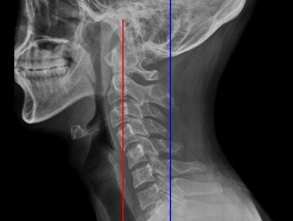

좋은 체형이란 보통 허리와 목 부분의 S자 모양의 자연스러운 만곡을 제외하고 수평적이고 수직적인 척추 위에 두개골(머리)이 균형 잡힌 채로 서 있는 것으로 이해된다. 반대로 나쁜 체형은 척추 전체가 과도한 S자형이거나 C자형이고 이런 척추 위에 머리와 어깨가 앞으로 쏠려 있게 되는 자세를 보통 말한다.

일자목은 잘못된 체형 중 대표적인 것이지만 단순히 근육을 풀어서 해결할 수 있는 문제는 아니며 흔하게 소개되는 운동 방법들 중에는 문제가 될 수 있는 동작들도 적지 않습니다.